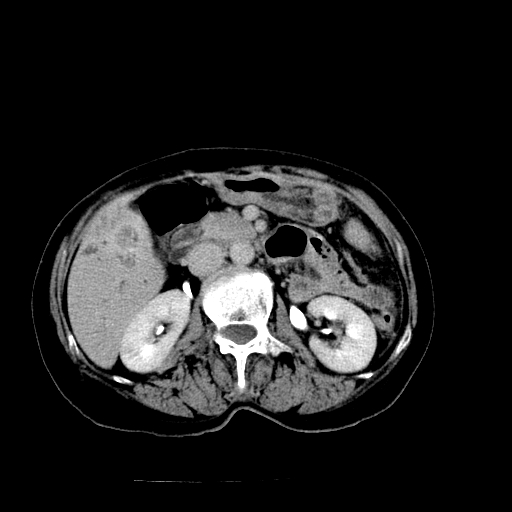

以下是引用随光逐影在2009-4-7 8:21:00的发言:[br]肝内外胆管多发性结石并肝内外胆管扩张;胆系感染。